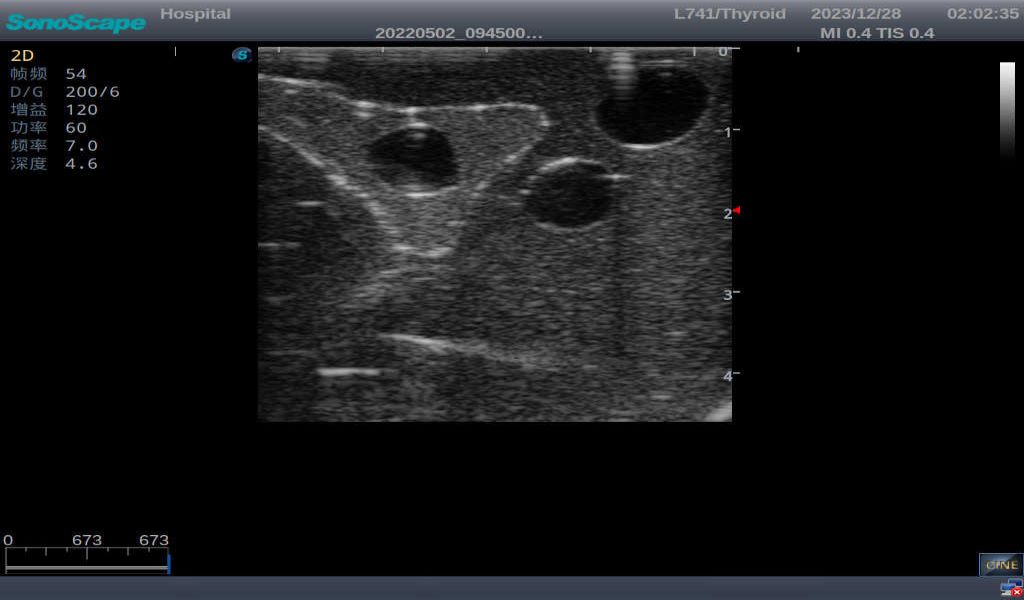

3)       It comes with four (4) thyroid modules and can show five (5) ultrasonic images: normal thyroid, thyroid adenoma, thyroid cancer, nodular goiter, thyroid cyst

Nodular goiter with irregular border and varying sizes of low echo, isoechoic, or high echo nodules

Thyroid cyst, which fluid area, dark and echo-free area can be seen